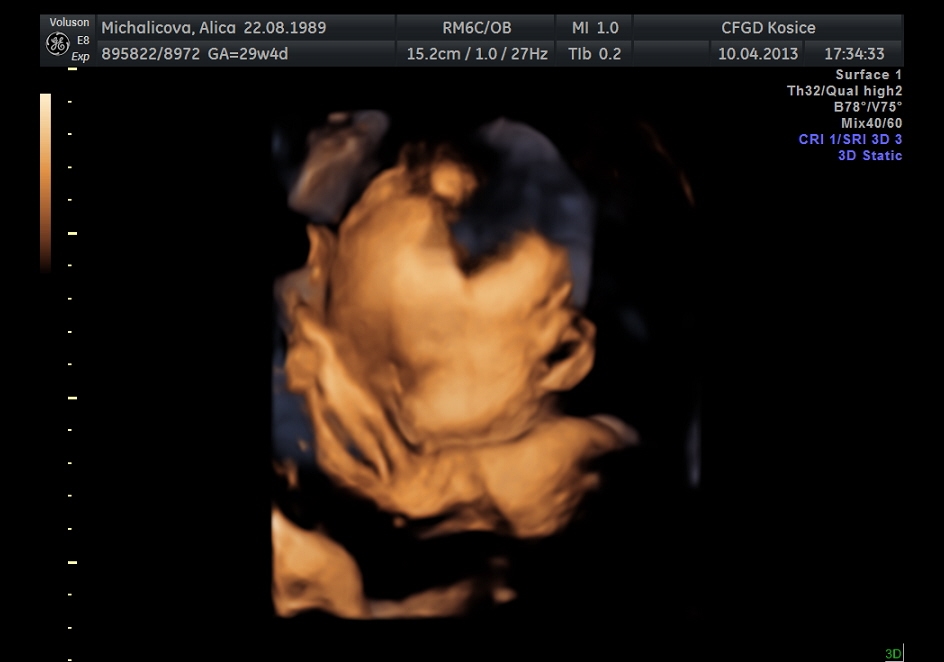

ahojte baby, tak máme za sebou 3D ultrazvuk som sa tešila že uvidim tváričku malej ale potvorka sa celý čas zakrývala ručkami tak vela toho nevidno 😀 ale nevadí no, hlavne že je všetko v poriadku má okolo 1550g... nezdá sa vám to vela na 30.tt?neviem to porovnať lebo pri prvej dcerke som nebola na 3D. Pekný dník prajem ešte pridám 2 fotky :o)